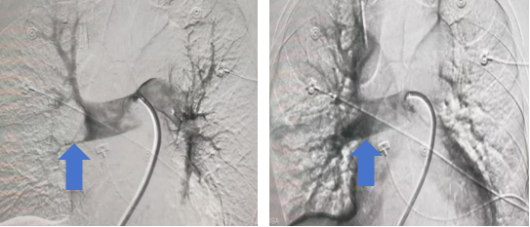

术中造影显示右侧肺动脉大块血栓,取栓后造影右侧肺动脉显影良好